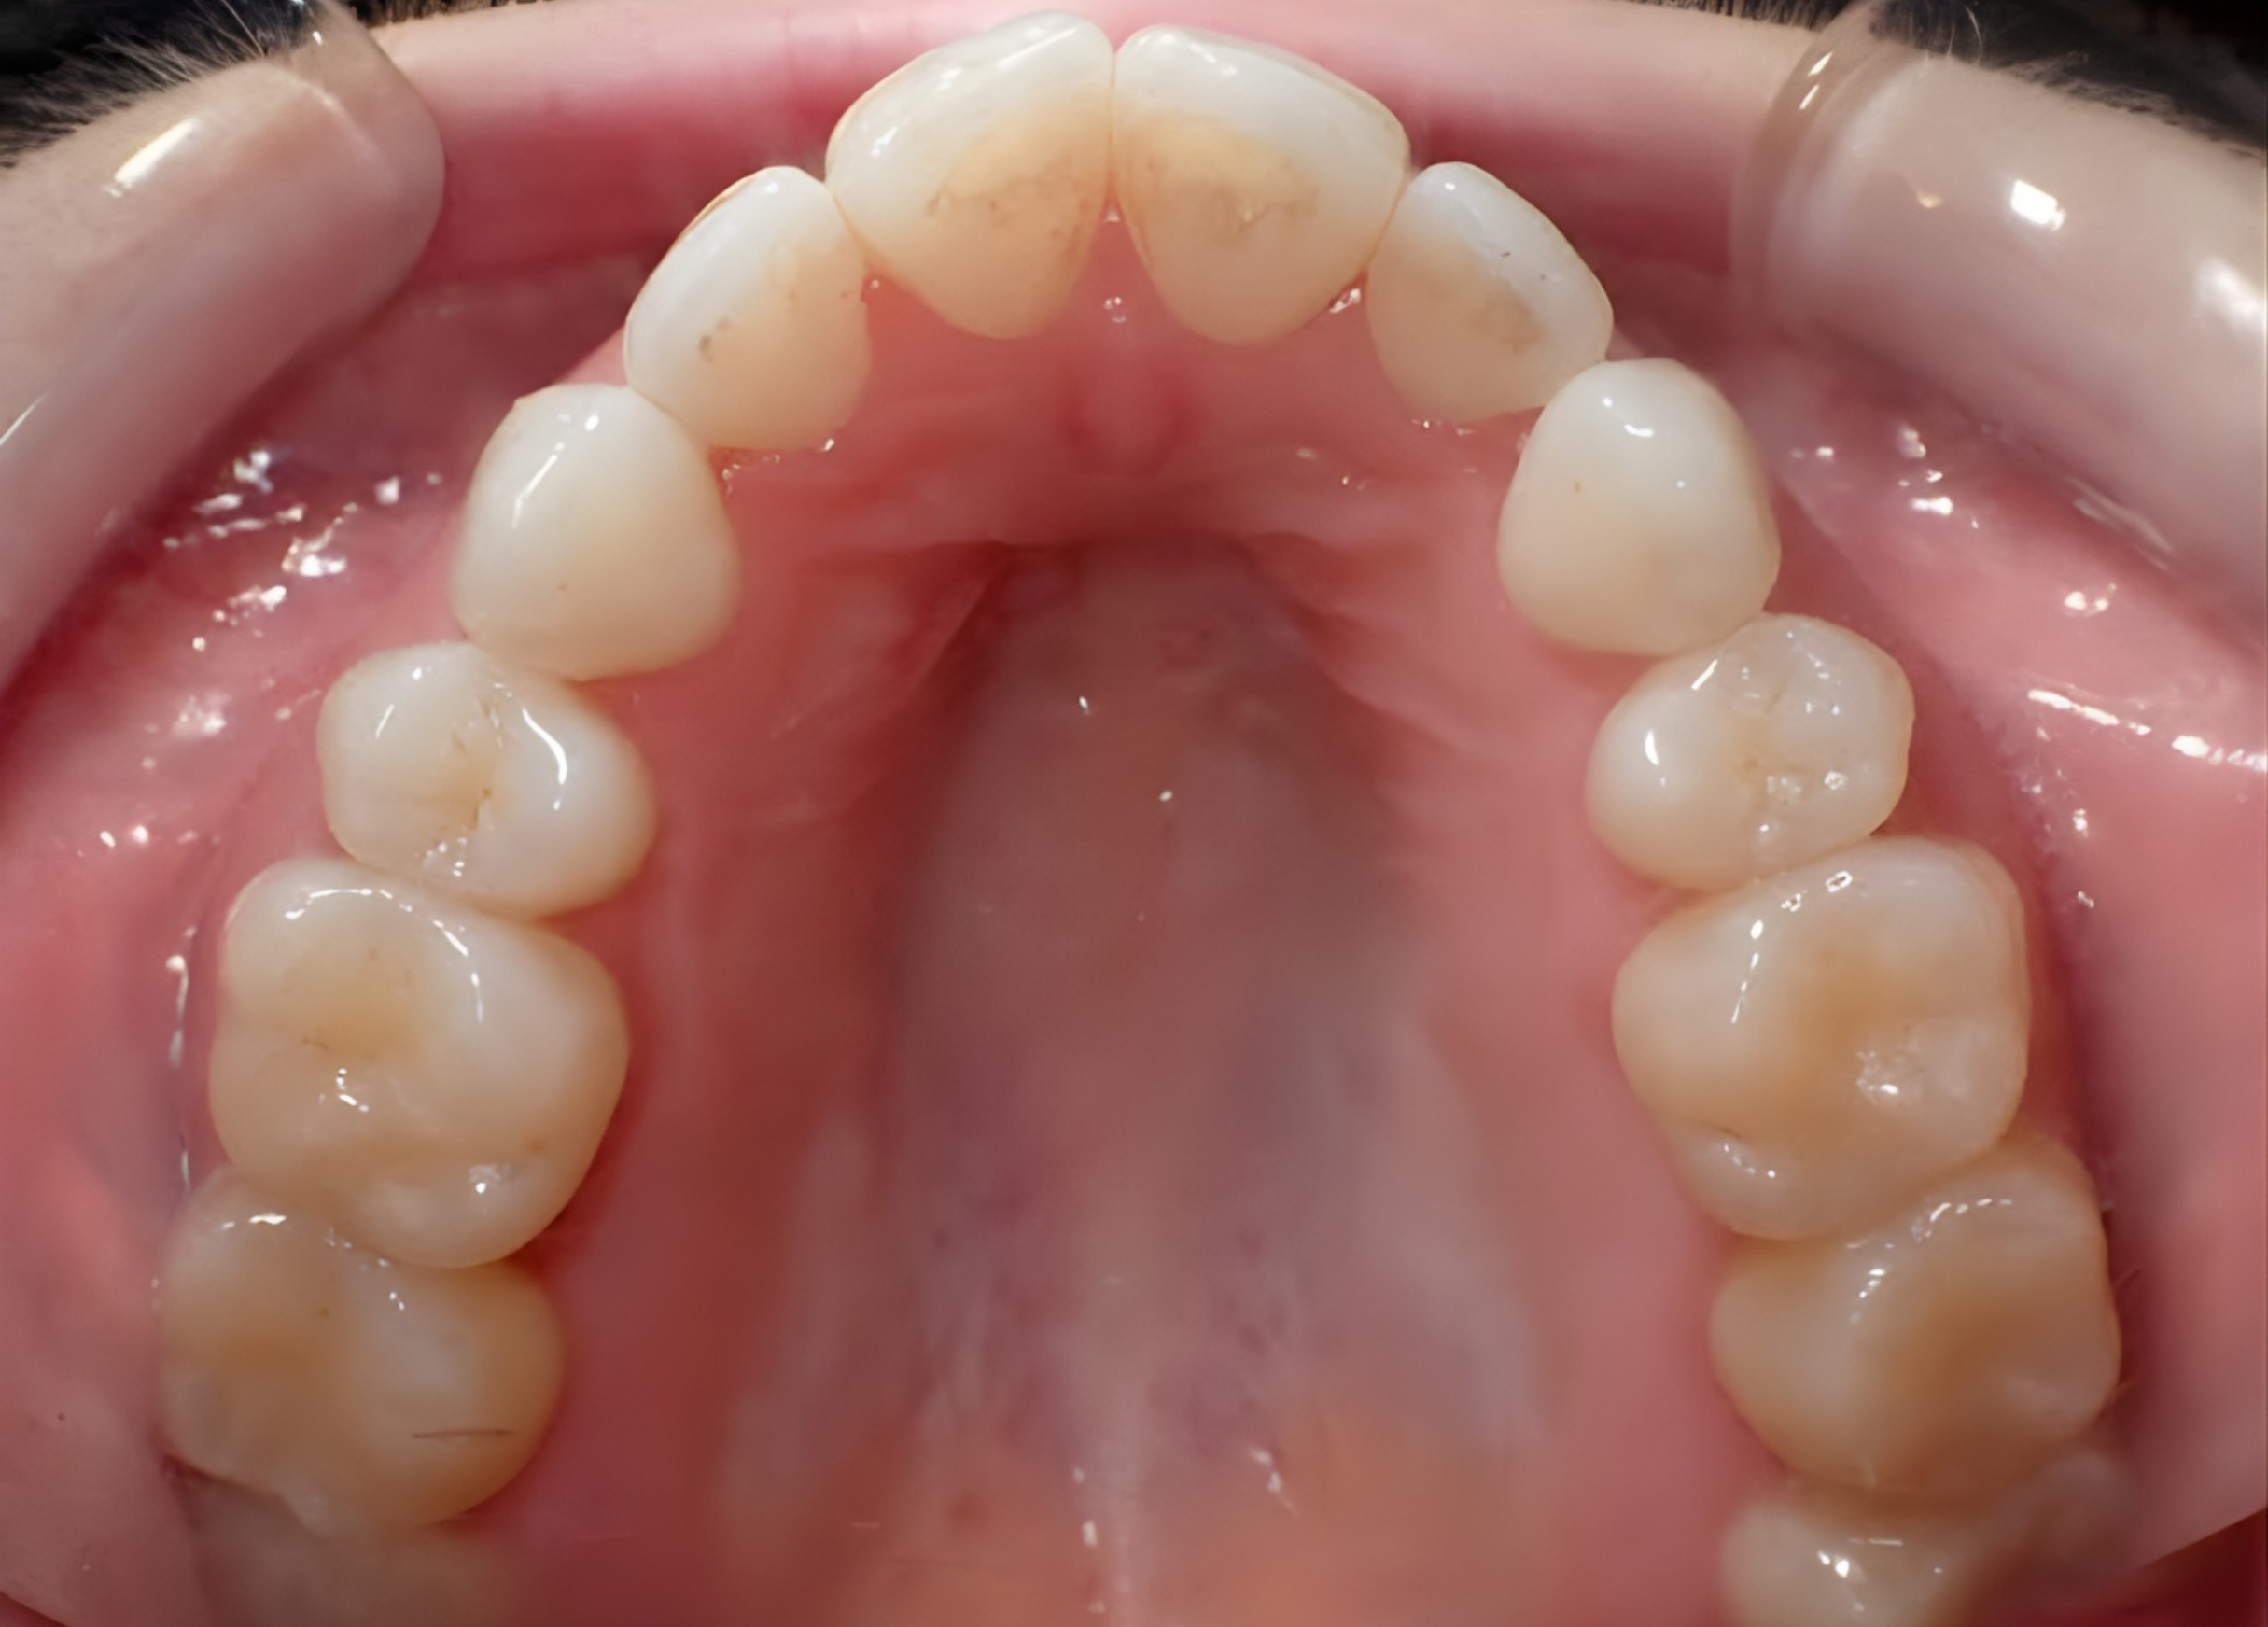

What is Maxillary Skeletal Expansion?

Maxillary Skeletal Expansion is an advanced orthodontic treatment designed to widen the upper jaw (maxilla) by gently separating the mid-palatal suture — the natural joint that connects the two halves of the upper jaw. Unlike traditional expanders that rely primarily on tooth movement, skeletal expansion focuses on creating true bone expansion. This approach improves jaw width, dental alignment, airway space, and overall facial balance. Maxillary Skeletal Expansion is often recommended for adolescents and adults whose jaw development is complete or nearly complete, where conventional expansion methods may be less effective.